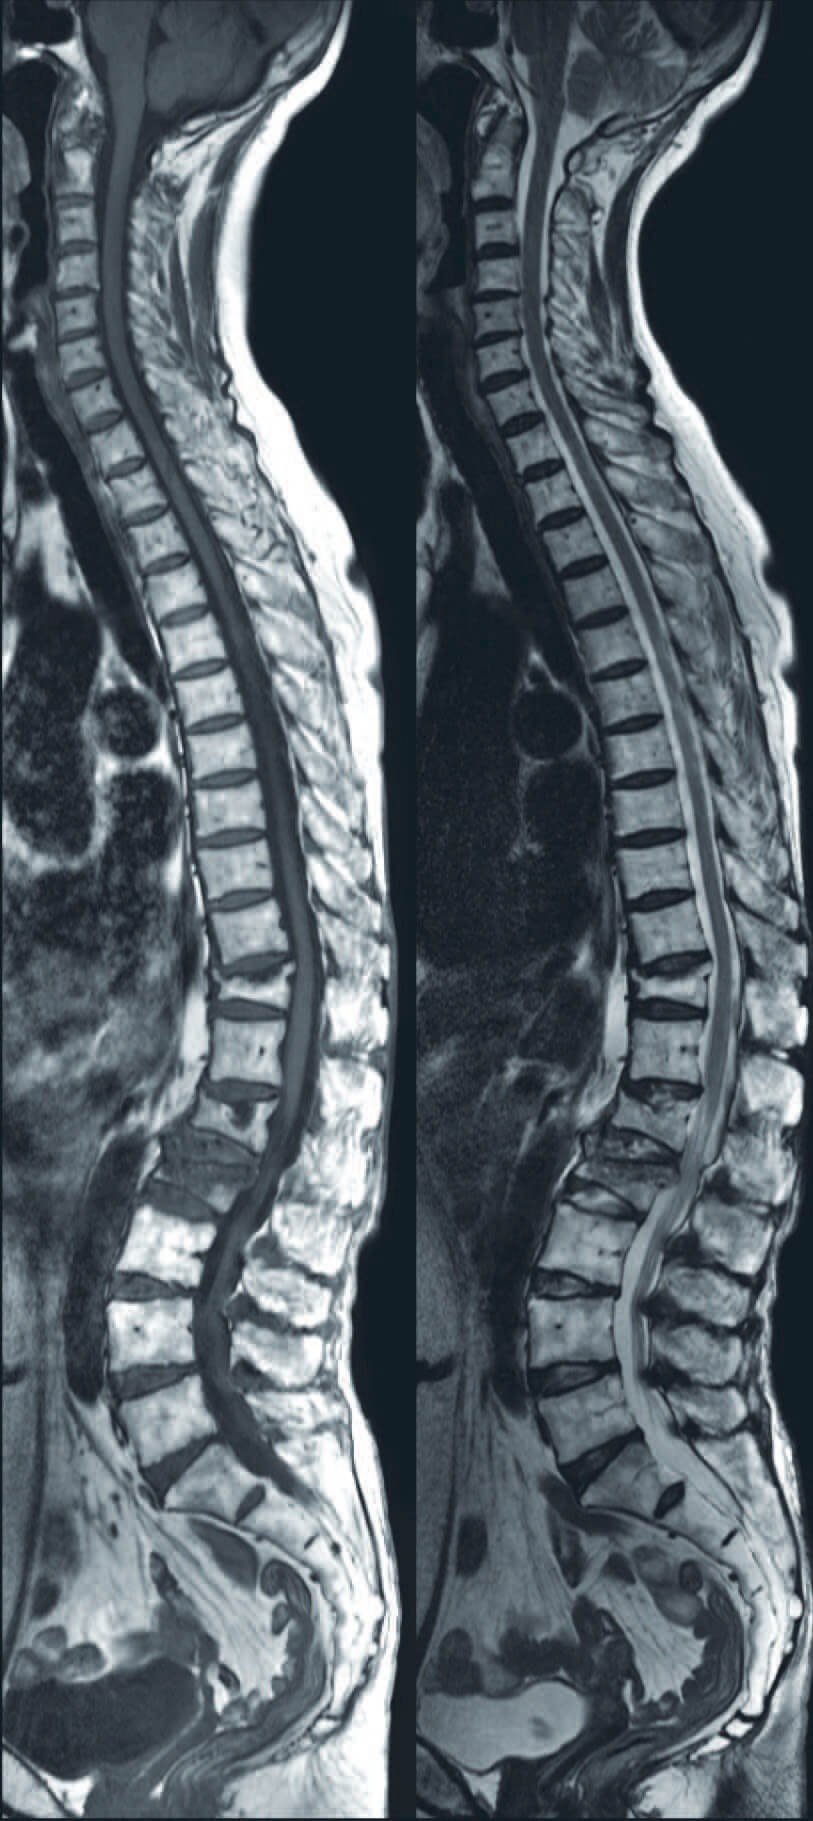

Spine